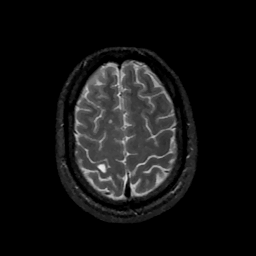

MR Study #11, May 5, 1991 -- Slice #41

[Home][Help][Clinical][Tour 1][Tour 2] Slice 41